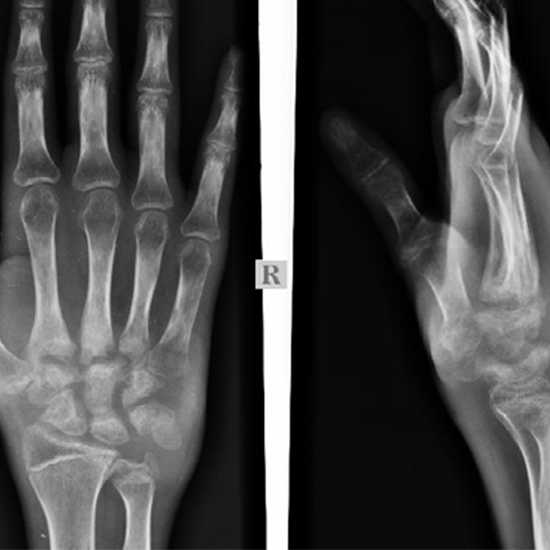

X-ray Right Hand AP/LAT

An X-ray of the hand shows the bones and the skin and muscles around them. The carpals are the bones in the wrist. The metacarpals are the bones between the wrist and the fingers. The phalanges are the bones in the fingers (bones of the fingers).